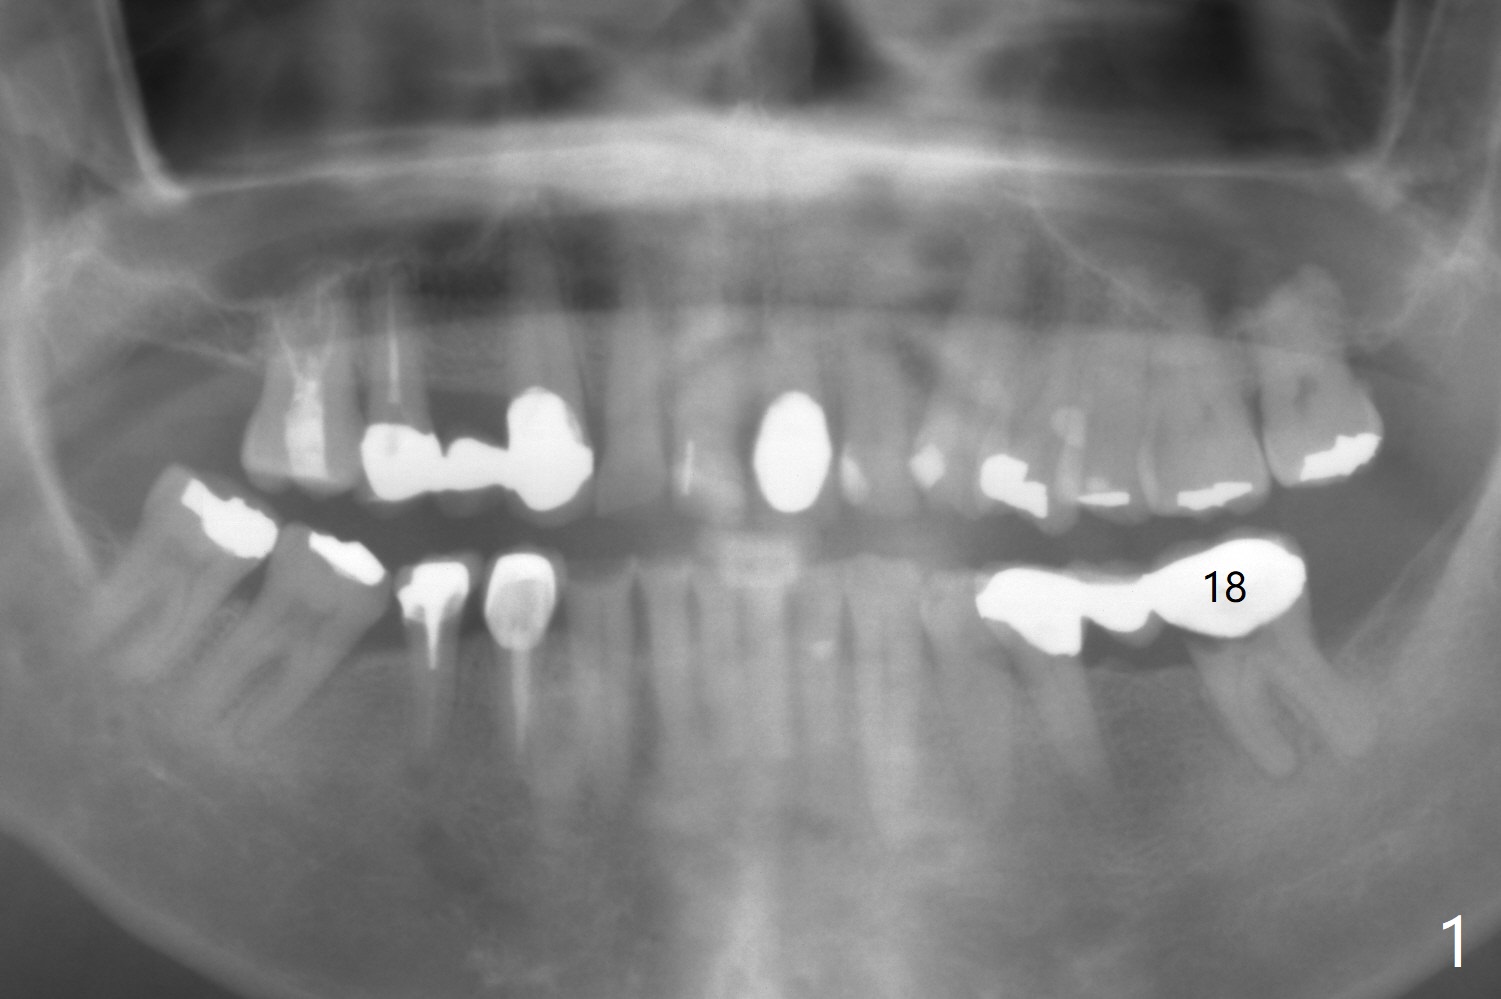

A 63-year-old man has lots of restoration (Fig.1), including #18-20 3-unit FPD. The latter has been sectioned to confirm non-salvageability of the tooth #18. After extraction and debridement, use a Rongeur purchased recently to flatten the pointed septum if present. Osteotomy is initiated with 1.6 mm and 2 mm pilot drills (parallel pin, PA), followed by sequential Magic Drills. If the septum is absent, use IS short stoppers to make osteotomy in the native bone (from the bottom of the socket). An incision will be made at the site of #19. If the edentulous ridge turns out to be narrow, choose a 1-piece implant. Otherwise use a Magicore. Take photos of the tooth #18 prior to extraction.